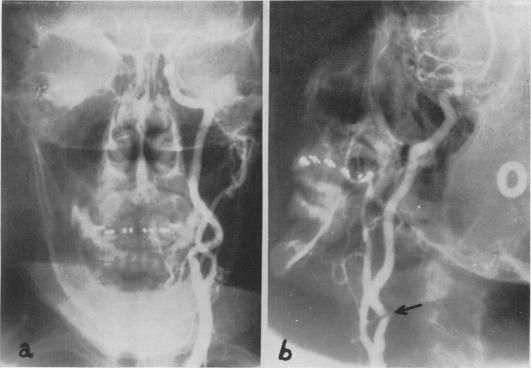

Critical evaluation and surgical correction of obstruction of obstruction in the branches of the aortic arch.

Ann Surg. 1960 Sep;152(3):472-84. doi: 10.1097/00000658-196009000-00010.